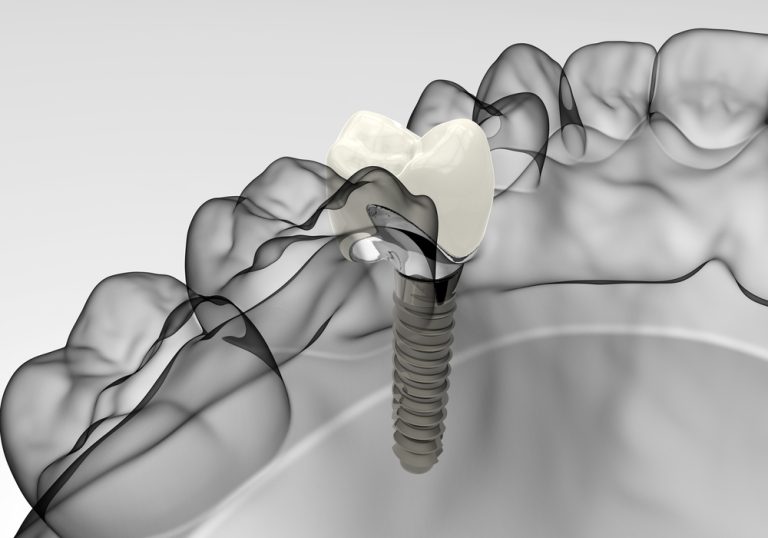

When to Consider Dental Implants in Chula Vista

If you are missing one or more teeth, a dental implant can help to prevent the teeth adjacent to the gap from tilting or shifting, which might misalign your bite and cause other dental problems. The teeth on the opposing jaw may also grow irregularly because there’s no mate to make contact with, causing you …

When to Consider Dental Implants | Chula Vista CA

If you are missing one or more teeth, a dental implant can help to prevent the teeth adjacent to the gap from tilting or shifting, which might misalign your bite and cause other dental problems. The teeth on the opposing jaw may also grow irregularly because there’s no mate to make contact with, causing you …